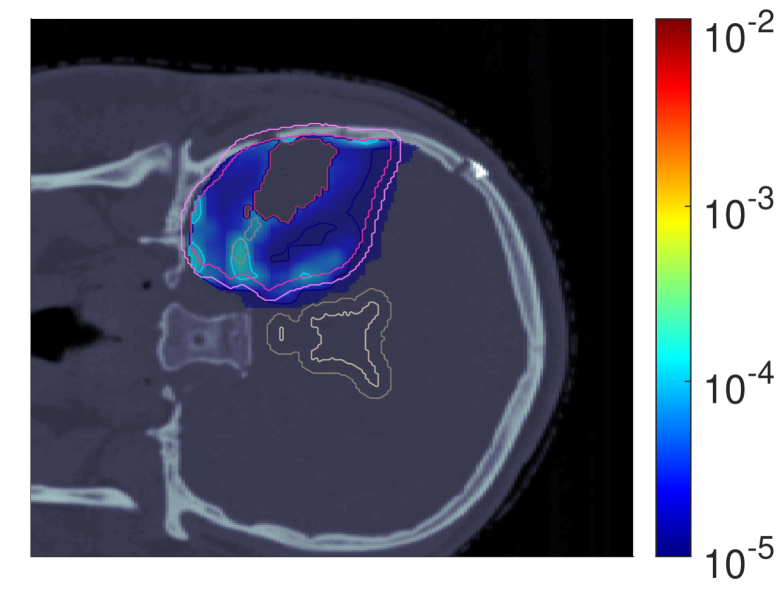

Figure 7 shows the POLO maps resulting from voxel-wise evaluation of the sigmoid-transformed linear predictor η\eta from Equation 1 with the input slice images for dRBE,fxd_{RBE,fx} and ldl_{d}.

NTCP30 %NTCP\approx{$30\text{\,}\mathrm{\char 37\relax}$} NTCP20 %NTCP\approx{$20\text{\,}\mathrm{\char 37\relax}$} NTCP10 %NTCP\approx{$10\text{\,}\mathrm{\char 37\relax}$}

pp (NTCPp)(NTCP_{p})

Refer to caption Refer to caption Refer to caption

pp (LSEp~)(LSE_{\tilde{p}})

pp (H~p)(\tilde{H}_{p})

pp (H~p~)(\tilde{H}_{\tilde{p}})

Figure 7: Optimal slice images of the probability of lesion origin pp for NTCPpNTCP_{p}, LSEp~LSE_{\tilde{p}}, H~p\tilde{H}_{p} and H~p~\tilde{H}_{\tilde{p}} at different NTCP levels. Considering the slice images for dRBE,fxd_{RBE,fx} and ldl_{d} from Figure 3 and Figure 5, the calculated pp values can be deduced from the prediction model. For example, hot spots are primarily found where high dRBE,fxd_{RBE,fx} values meet high ldl_{d} values, and for the voxels inside the 4 mm4\text{\,}\mathrm{mm} ventricular fringe where bb boosts the probability prediction. We take from these results that the POLO model-based optimization of the LGG sample patient’s proton plan achieves its goal, i.e., reducing pp in the region of interest.

For NTCPpNTCP_{p} and H~p\tilde{H}_{p}, we observed a (slight) reduction of dRBE,fxd_{RBE,fx} in the target volume and in the lower region overlapping with the VS, as well as a redistribution of ldl_{d} from the target volume to the margin of the PTV. Correspondingly, we see an overall reduction of pp in the target volume, together with an increasing attenuation of the hot spots around the marginal region of the PTV, and an elimination at the lower end of the VS. At strong down-regulation of the NTCP, the values are approximately one order of magnitude smaller, with peaks in the intersections to the 4 mm4\text{\,}\mathrm{mm} ventricular fringe and in regions where dRBE,fxd_{RBE,fx} and ldl_{d} intensify.

LSEp~LSE_{\tilde{p}} showed a decay of dRBE,fxd_{RBE,fx} inside but not outside the target volume, and almost constant values of ldl_{d}, and we recognize this pattern again in the pp distributions: hot spots are softened by the isolation of high-dose and high-LET regions, and the pp values in the target volume follow the negative trend for dRBE,fxd_{RBE,fx} at lower NTCP levels. Even the “dose gap” that occurs at an NTCP of 20 %20\text{\,}\mathrm{\char 37\relax} in the upper part of the target volume can be read from pp. Last, for H~p~\tilde{H}_{\tilde{p}} we can correlate the results for dRBE,fxd_{RBE,fx} and ldl_{d} again to understand pp. The higher ldl_{d} along the PTV margin is reflected by larger pp values and local hot spots, while the region around the GTV exhibits smaller pp values due to the reduction of dRBE,fxd_{RBE,fx}. At the lowest NTCP level, dRBE,fxd_{RBE,fx} contracts around the GTV, leaving only a slightly upward region at the left margin of the PTV which resembles the high-LET region, and hot spots where dRBE,fxd_{RBE,fx}, ldl_{d} and bb interact reinforcingly.

Globally, we observe an analogous shift in the “mass” of the pp distribution to lower values from the histograms in Figure 8. This indicates that the overarching goal of reducing pp during optimization can be fulfilled.